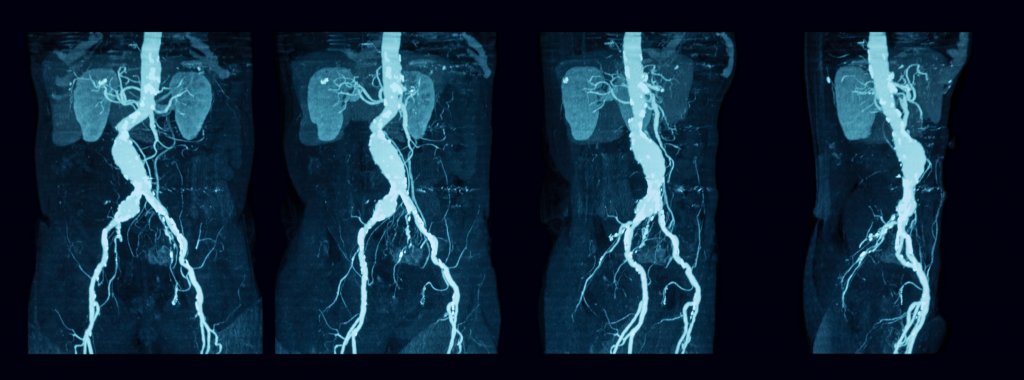

A catheter (a long, thin, flexible tube) is inserted into a vein in your groin or neck and fed into the pulmonary artery (see diagram below). A specialist then injects a dye into the arteries of the lungs through the catheter. The dye helps to highlight any blockages to blood flow (e.g. blood clots) on the pictures of the lungs taken by the X-ray machine.